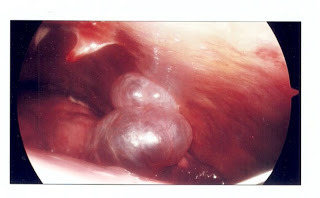

These balloon-like objects are bleb, which are are air-filled blisters on the surface of the lungs. A bleb can rupture at any time and cause a pneumothorax, which is a collapsed lung.

A collapsed lung is dangerous and very painful. One day in January 2013 I checked in to the local ER with chest pains and shortness of breath, and a chest x-ray revealed a "huge" pneumothorax, which looked something like the x-ray above.

I was soon given my very own chest tube, which I wouldn't wish on...